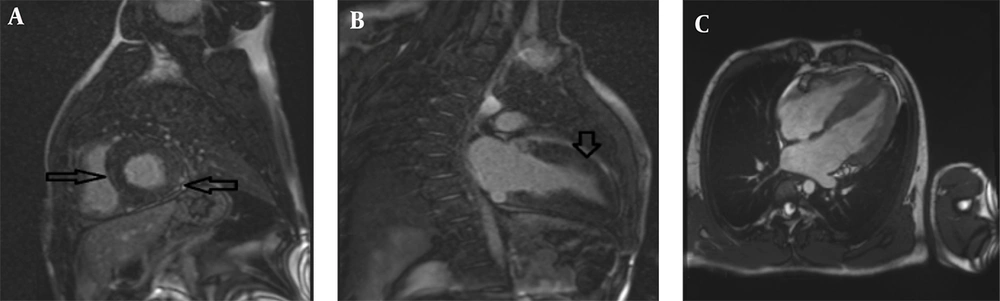

A 14-year-old female (height: 159 cm, weight: 60 kg, BSA: 1.6 m2) with a clinical diagnosis of FA but no significant extra-cardiac symptoms underwent cardiac MRI with the standard protocol. Morphological evaluation showed localized LVH in the mid-inferior septum with a maximum wall thickness of 14.6 mm. Both LV and RV size were normal with preserved systolic function (LVEF = 61%, RVEF = 58%); the LV Mass Index was 58 g/m2. Critically, tissue characterization found no significant fibrosis on LGE, and T1/T2 mapping values were within normal limits, effectively ruling out diffuse fibrosis or active inflammation (Figure 3). These findings suggested only mild cardiac involvement in FA for this patient.

Cardiac magnetic resonance (CMR) of a 14-year-old female with Friedreich’s ataxia: A, 2-Chamber Magnitude late gadolinium enhancement (LGE) imaging showing no significant fibrosis; B, 4-Chamber phase sensitive inversion recovery (PSIR) LGE image is within normal limits, indicating no diffuse fibrosis: C, 4-Chamber magnitude LGE images showing no significant fibrosis and LVH with maximum thickness :14.5mm, ruling out inflammation.

The fourth patient was a 22-year-old male (height: 170 cm, weight: 73 kg, BSA: 1.87 m2) with FA but without significant neurological progression. Following the standardized cardiac MRI protocol, morphological analysis demonstrated concentric LVH with a maximum wall thickness of 15 mm in the basal anterior septum. Functional status was notable for normal LV size with mildly reduced systolic function (LVEF = 46%), and normal RV size and function (RVEF = 60%); the LV Mass Index was 82 g/m2. Moderate aortic (AI), MR, and TR regurgitation were also observed. Tissue characterization identified patchy fibrosis in multiple myocardial segments on LGE imaging (Figure 4). In conclusion, the imaging findings, including hypertrophy, fibrosis, and valvular regurgitation, were consistent with significant cardiac involvement in FA.

Cardiac magnetic resonance (CMR) of a 22-year-old male with Friedreich’s ataxia (FA): A, Short axis phase sensitive inversion recovery (PSIR) late gadolinium enhancement (LGE) imaging revealing patchy fibrosis in multiple myocardial segments with arrows indicating affected areas; B, 2-Chamber PSIR LGE imaging further highlighting the extent of fibrosis in a different plane; C, Corresponding 4chamber cine steady-state free precession (SSFP) image demonstrating left ventricular hypertrophy (LVH) with maximum 15 mm thickness.